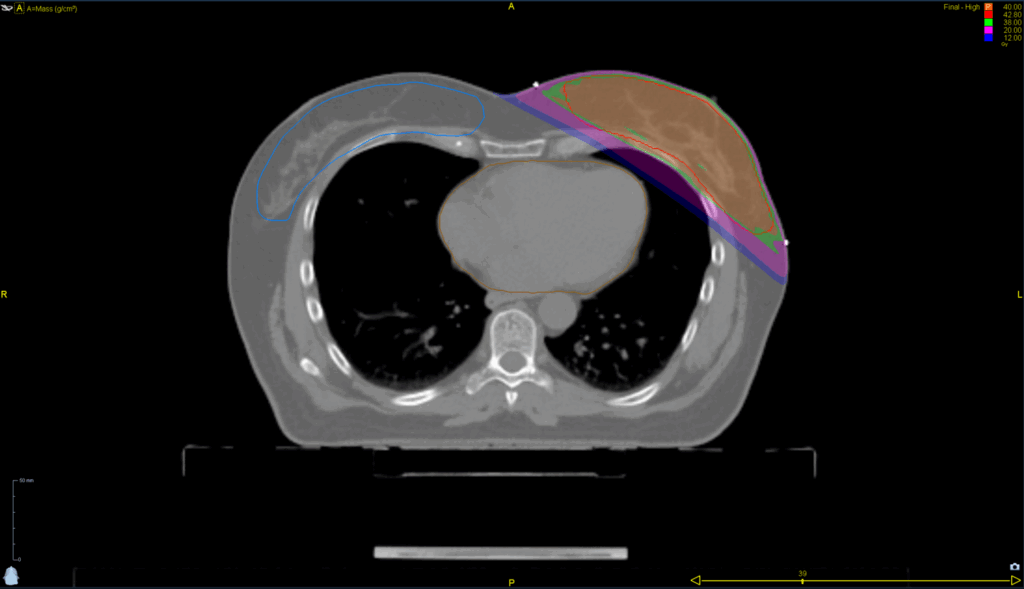

Treatment Plan Images

Fractionation / Protocol Used

40 Gy in 15 fractions

- TomoDirect™

- 4 angles

- TomoEDGE™ 5 cm